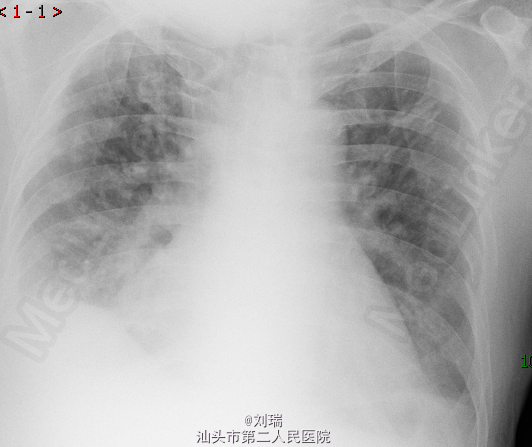

查体:急性面容,血压:110/90mmHg,心率116次/分,皮氧:99%,双肺可闻及少许哮鸣音;腹部膨隆;双下肢浮肿。患者D-二聚体由入院时470ug/L升至1090ug/L;床边胸片(图2)对比入院时(图1):见心影增大。